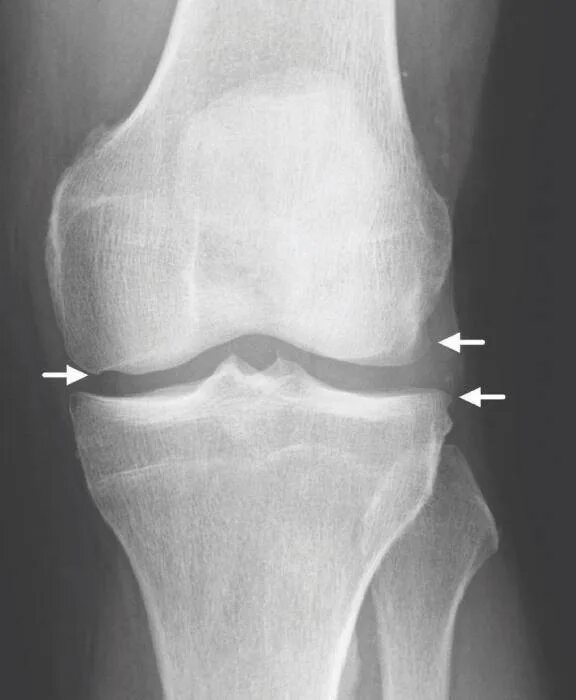

Деформирующий остеоартроз коленного сустава 1